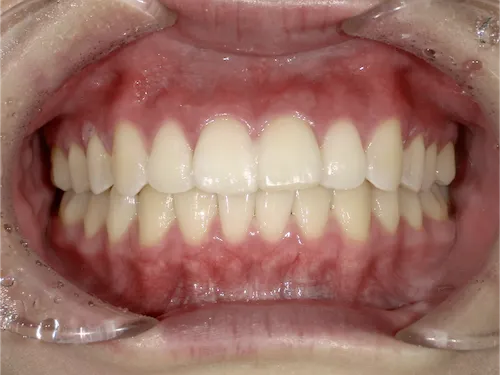

痛くない・しみないのに、45分で白くなる。

45分で白くなる。